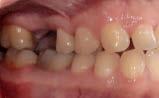

Caso clínico: paciente femenino de 19 años, patrón dolicofacial, perfil convexo, clase II esqueletal debido a una retrusión mandibular, mordida abierta anterior esqueletal, clase II molar, clase canina no establecida por mordida abierta, apiñamiento severo superior e inferior y deglución atípica.

Resultados: obtención de una clase canina I y clase molar II funcional, se corrigieron las sobremordidas horizontal y vertical, y se logró la coincidencia de líneas medias facial y dental. El manejo de la mordida abierta anterior se llevó a cabo por medio de la corrección del hábito de deglución atípica con la ayuda de spikes de resina, elásticos intermaxilares y arcos utility, y se obtuvieron buenos resultados estéticos, dentales y funcionales.